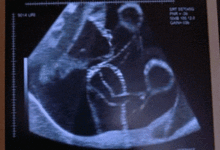

20周胎儿系统B超检查,又称为大排畸检查,是孕期中的一项重要检查。这一阶段的胎儿已经发育到一定程度,器官结构基本形成,通过B超检查可以全面了解胎儿的生长发育情况,及时发现并排除严重的胎儿畸形。

一般来说,20周胎儿系统B超检查的最佳时间为妊娠20-24周。此时,胎儿各器官已经发育成熟,羊水量适中,胎儿相对容易变换体位,有利于超声筛查胎儿结构。